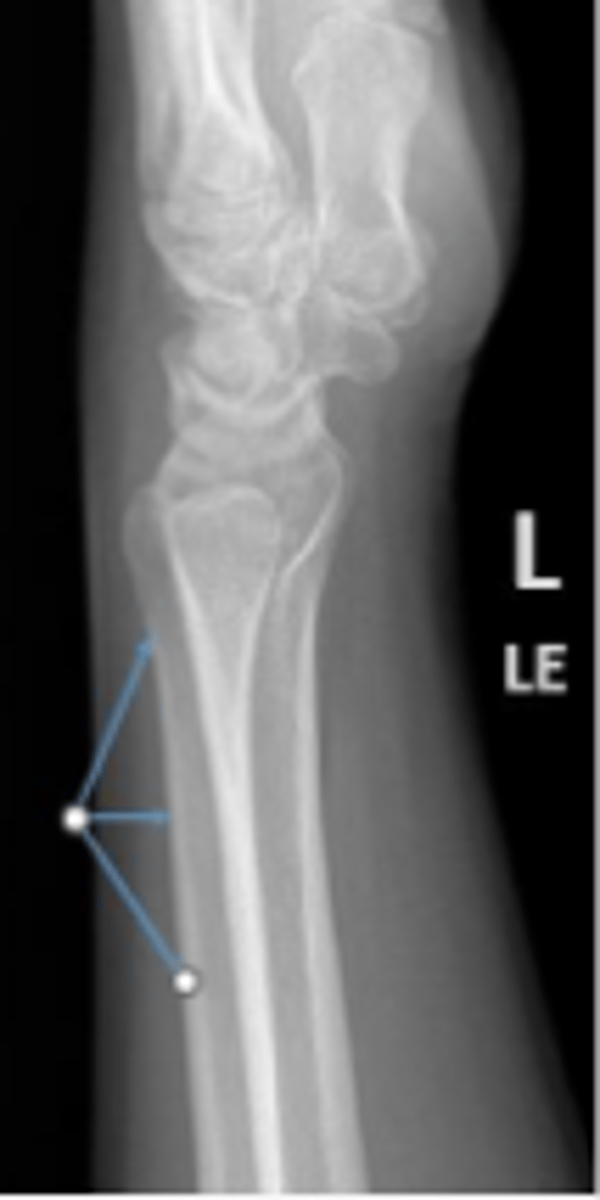

PA of the left wrist

What is the name of the radiographic view?

3 arcs of carpal alignment

What is the name of the assessment

Proximal cortical aspect of the first (proximal)

carpal row (ARC 1)

What are the landmarks for the most proximal line in the assessment?

Distal cortical aspect of the first (proximal) carpal

row (ARC 2)

What are the landmarks for the most middle line in the assessment?

Proximal cortical aspect of the second (distal)

carpal row (ARC 3)

What are the landmarks for the most distal line in the assessment?

SLAC wrist; carpal dislocation, carpal fracture

Name 2 conditions that will result in an alteration of the assessment?